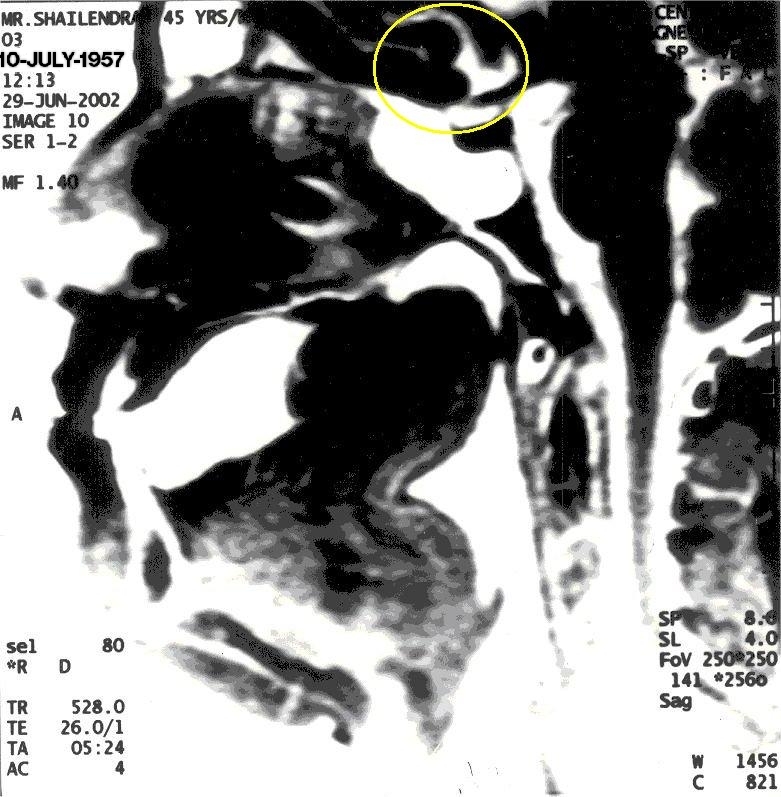

MRI of Shailendra Sharma in Khechari Mudra

With Khechari Mudra, notice the formation of an 'Om' like impression (highlighted in yellow)